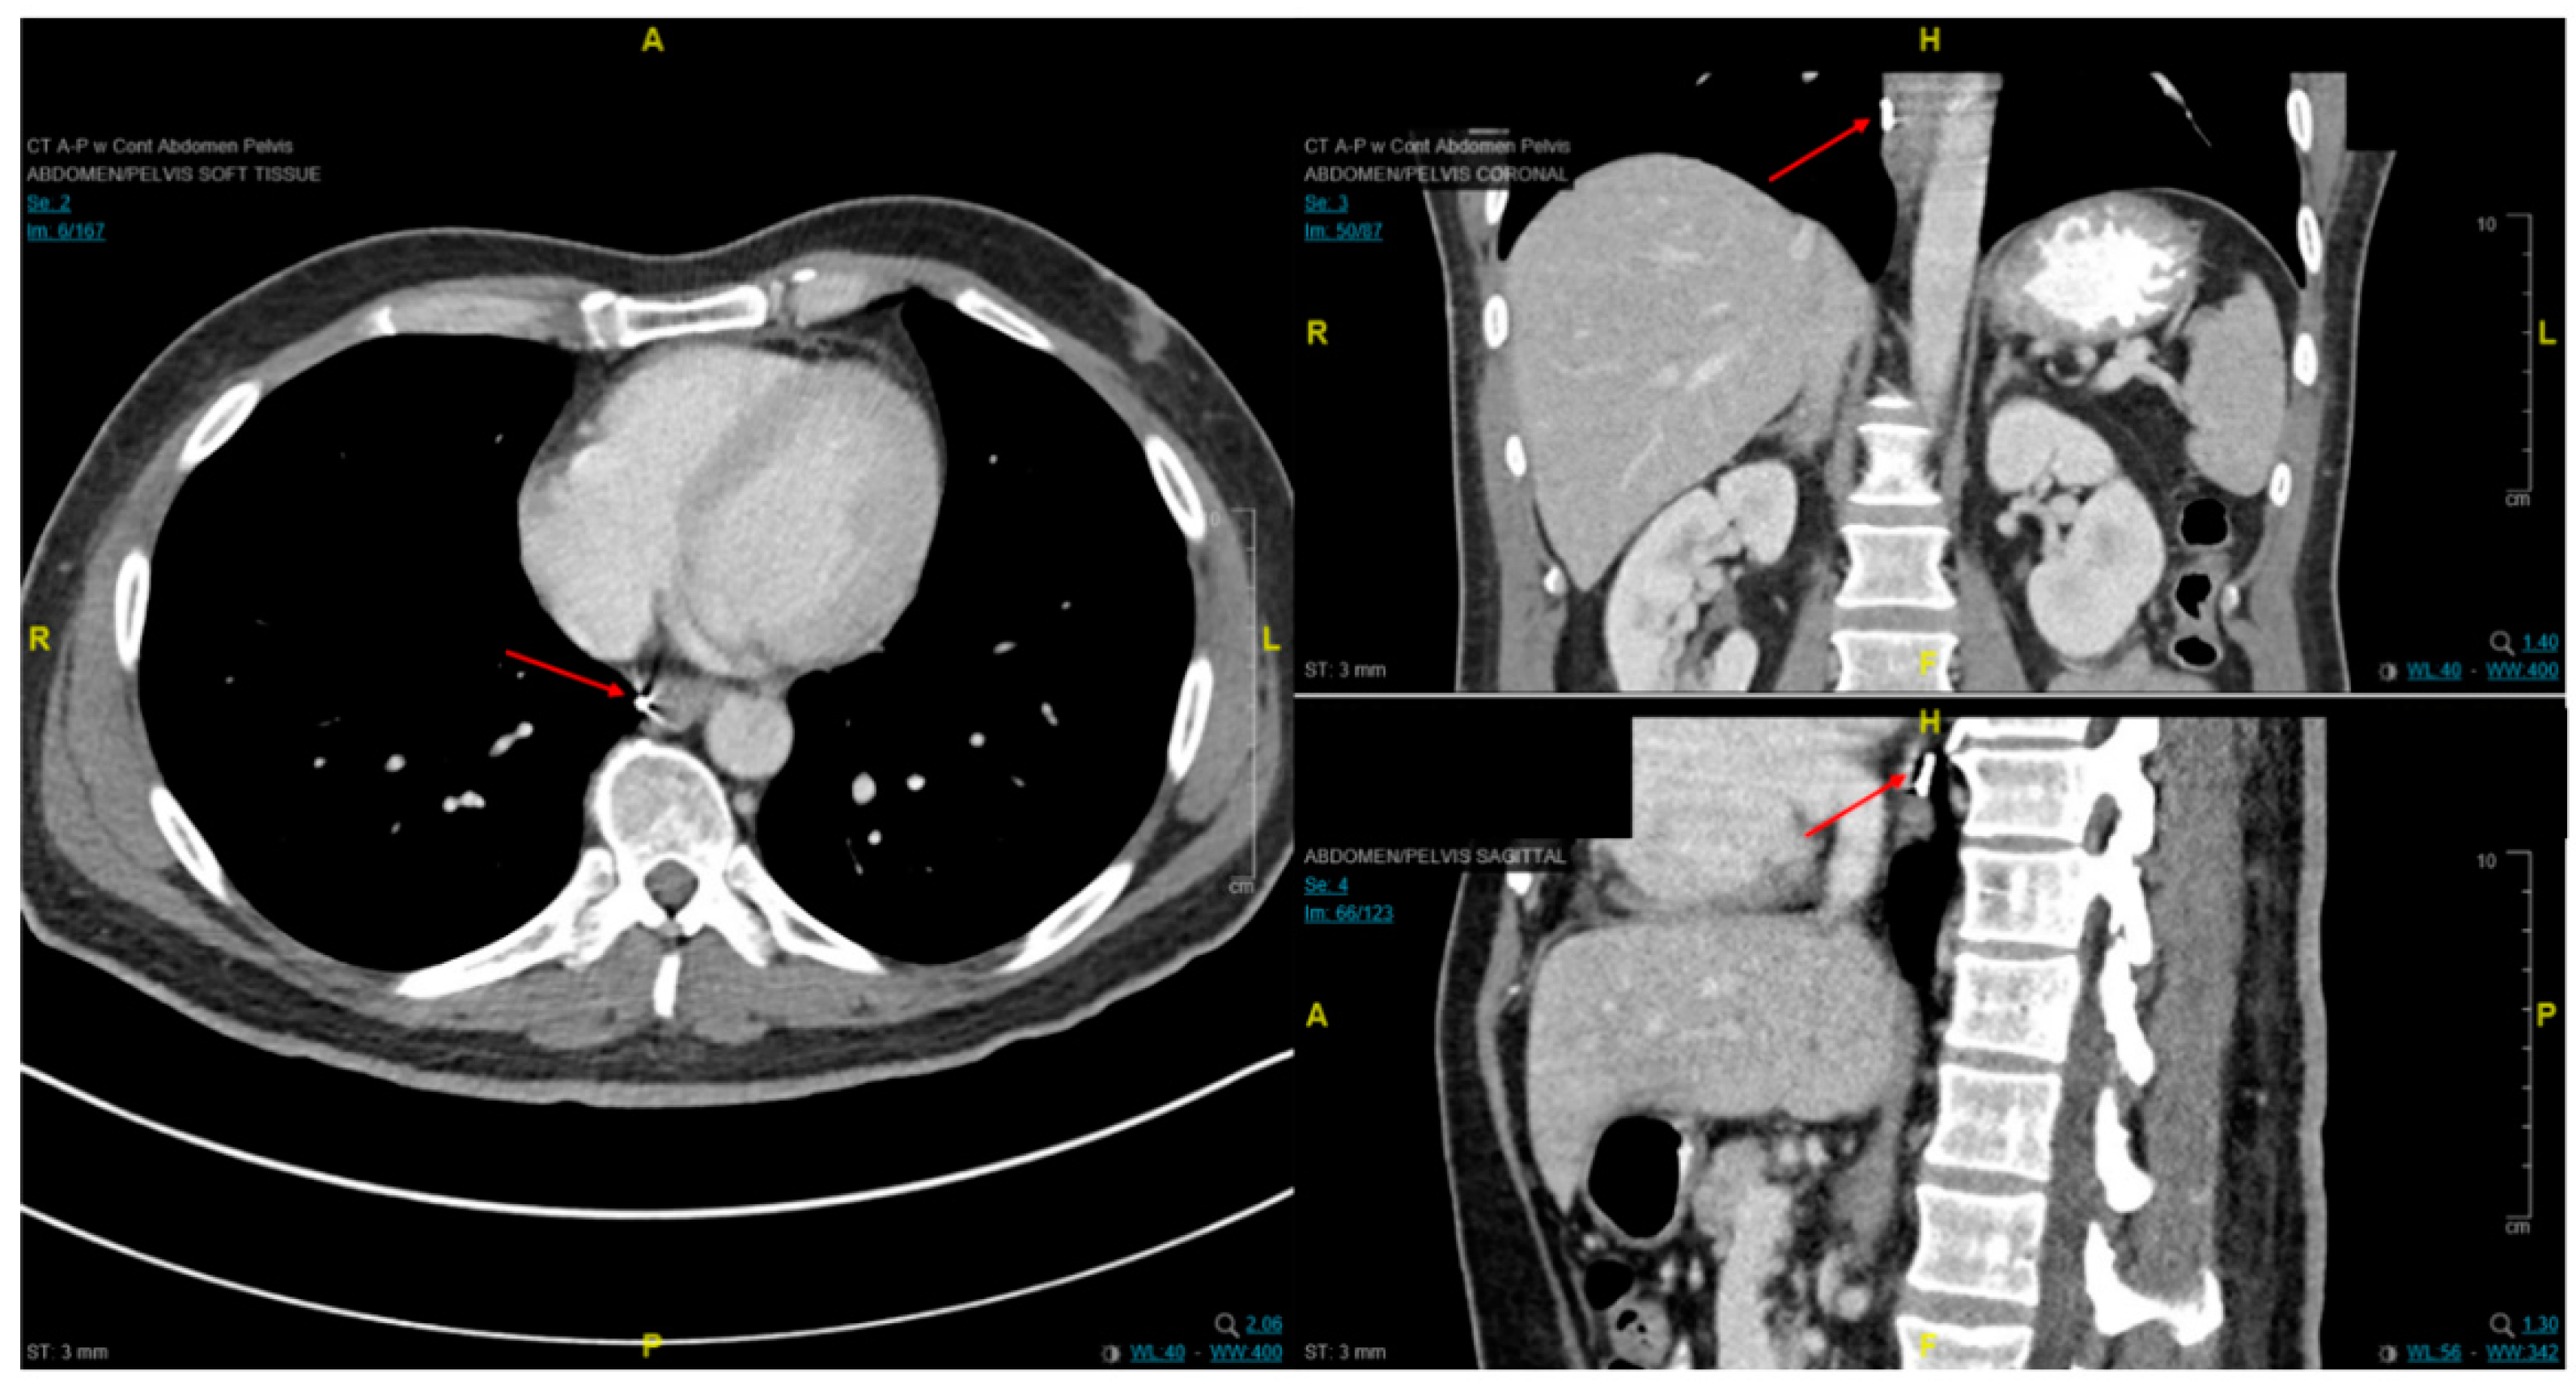

2.2. Distant and Locoregional Staging

4.3. Endoscopic Ultrasound in Staging of Gastric Cancer